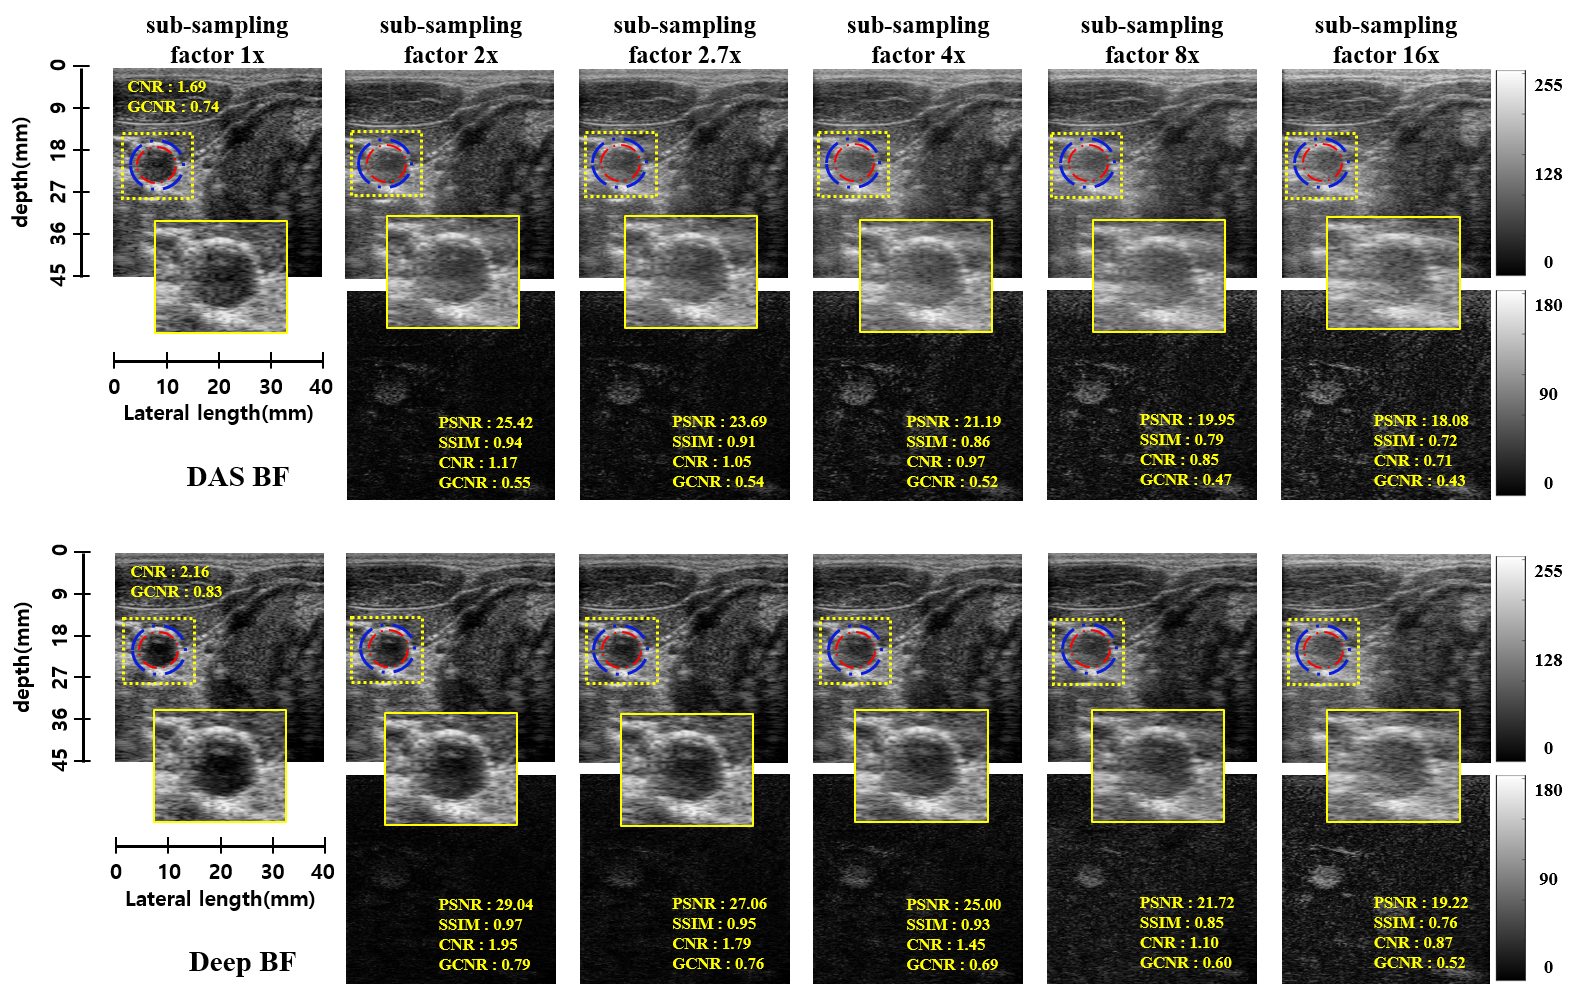

Figs. 5 show the results of an in vivo example for the full data (i.e. channel) as well as , , , and Rx-channels down-sampling schemes. Since 64 channels are used as a full sampled data, this corresponds to and sub-sampling factors. The images are generated using the proposed DeepBF and the standard DAS beam-former method. Our method significantly improves the visual quality of the US images by estimating the correct dynamic range and eliminating artifacts for both sampling schemes. From difference images, it is evident that the quality degradation of images in DAS is higher than the DeepBF. Note that the proposed method successfully reconstruct both the near and the far field regions with equal efficacy, and only minor structural details are imperceivable. Furthermore, it is remarkable that the CNR and GCNR values are significantly improved by the DeepBF even for the fully sampled case (eg. from to in CNR and from to in GCNR), which clearly shows the advantages of the proposed method. It is believed that this is due to performance boosting behavior similar to super-resolution deep neural networks in which the authors have found that multiple-magnification training outperforms fixed-magnification cases [6]. Additional results on phantom dataset are available in supplemental document.

Fig 5 shows the reconstruction results on phantom dataset. We also compared the CNR, GCNR, PSNR, and SSIM distributions of reconstructed B-mode images obtained from phantom test frames. Table 3 showed that the proposed deep beamformer consistently outperformed the standard DAS beamformer for all subsampling schemes and ratios.

5.0.1 Focused mode imaging results on phantom dataset

We also compared the CNR, GCNR, PSNR, and SSIM distributions of reconstructed B-mode images obtained from in-vivo test frames. Table 2 showed that the proposed deep beamformer consistently outperformed the standard DAS beamformer for all subsampling schemes and ratios. One big advantage of ultrasound image modality is it run-time imaging capability, which require fast reconstruction time. Another important advantage of the proposed method is the run-time complexity. The average reconstruction time for each depth planes is around (milliseconds), which could be easily reduce by optimized implementation and reconstruction of multiple depth planes in parallel.